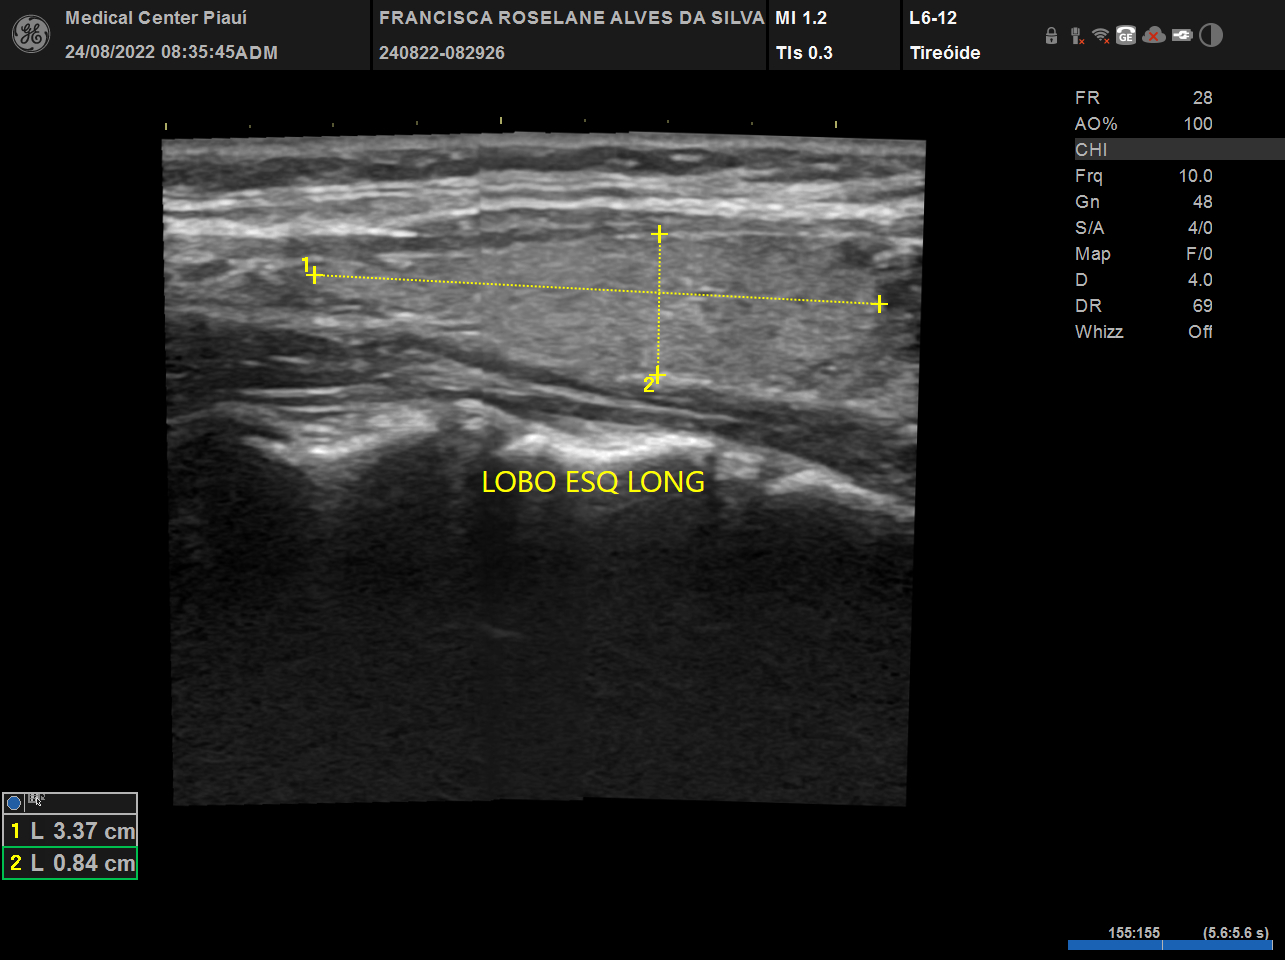

Tireoide

USG, TC e RN de tireoide

Vamos esclarecer as principais dúvidas de como tratar os portadores de hipotireoidismo, hipertireoidismo, nódulo de tireoide, câncer de tireoide. Além disso um treinamento sobre ultrassonografia de tireoide, PAAF e alcoolização percutânea de nódulos (IPE). Ao final, estar apto a decidir quando usar medicações, operar ou usar radioiodoterapia.